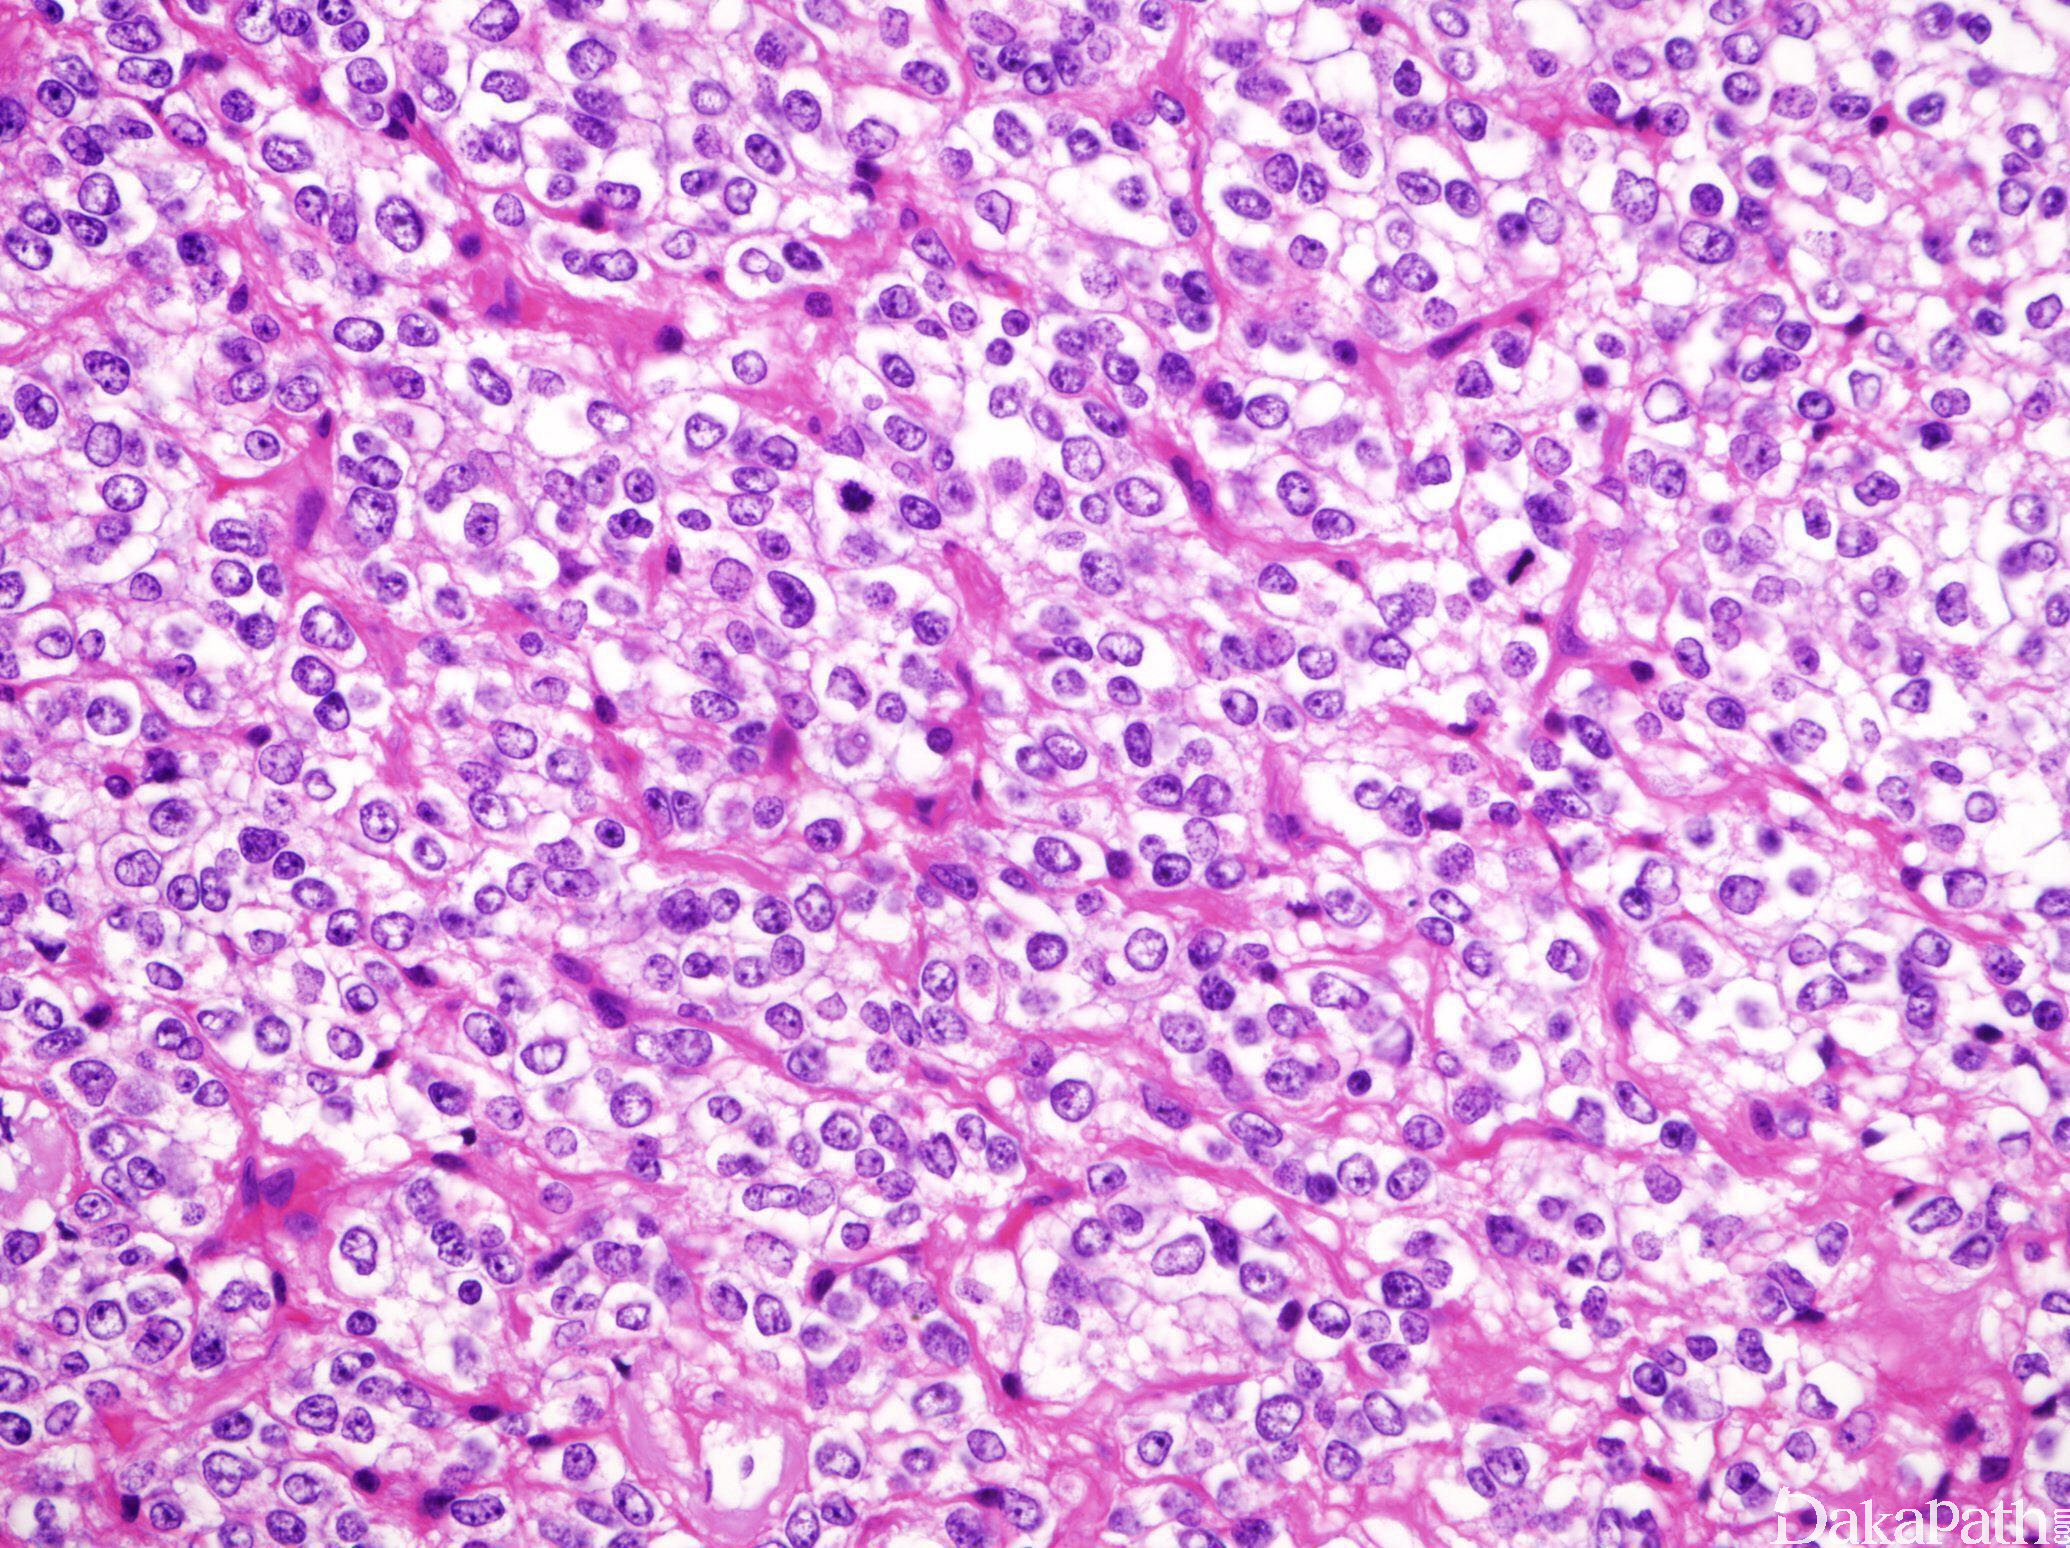

细胞特点:密度可极低至较高,富于细胞的结节常伴核分裂增多。胞浆无色透明(煎蛋样改变),细胞紧密排列,边界清楚。可见光滑的楔形细胞伴顶端玻璃样或纤维性包涵体(胶质纤维性少突胶质细胞),或小的肥胖星形细胞样细胞伴透明纤维性胞浆及短胞突;

血管成分:纤细分支状(铁丝网样)毛细血管;

III 级肿瘤:可见胞浆内强嗜酸性颗粒。胞核呈上皮样改变的胞界清楚的大圆形细胞尤为多见。可见血管肥大/增生,肾小球样血管不常见。常见球形钙化;